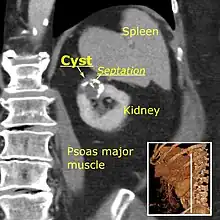

Simple renal cyst.jpg

Simple renal cyst